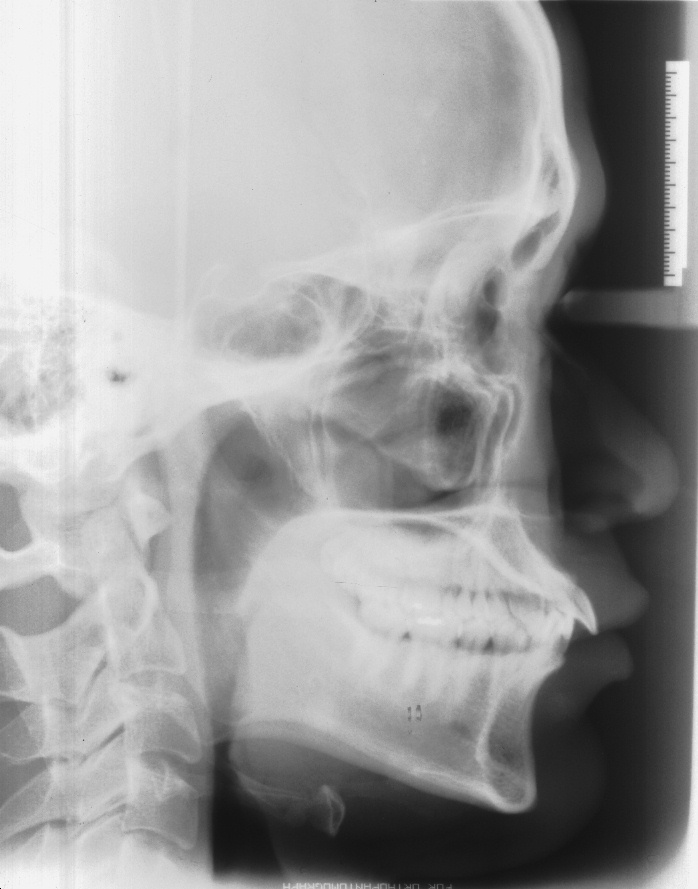

치료 전 사진입니다.